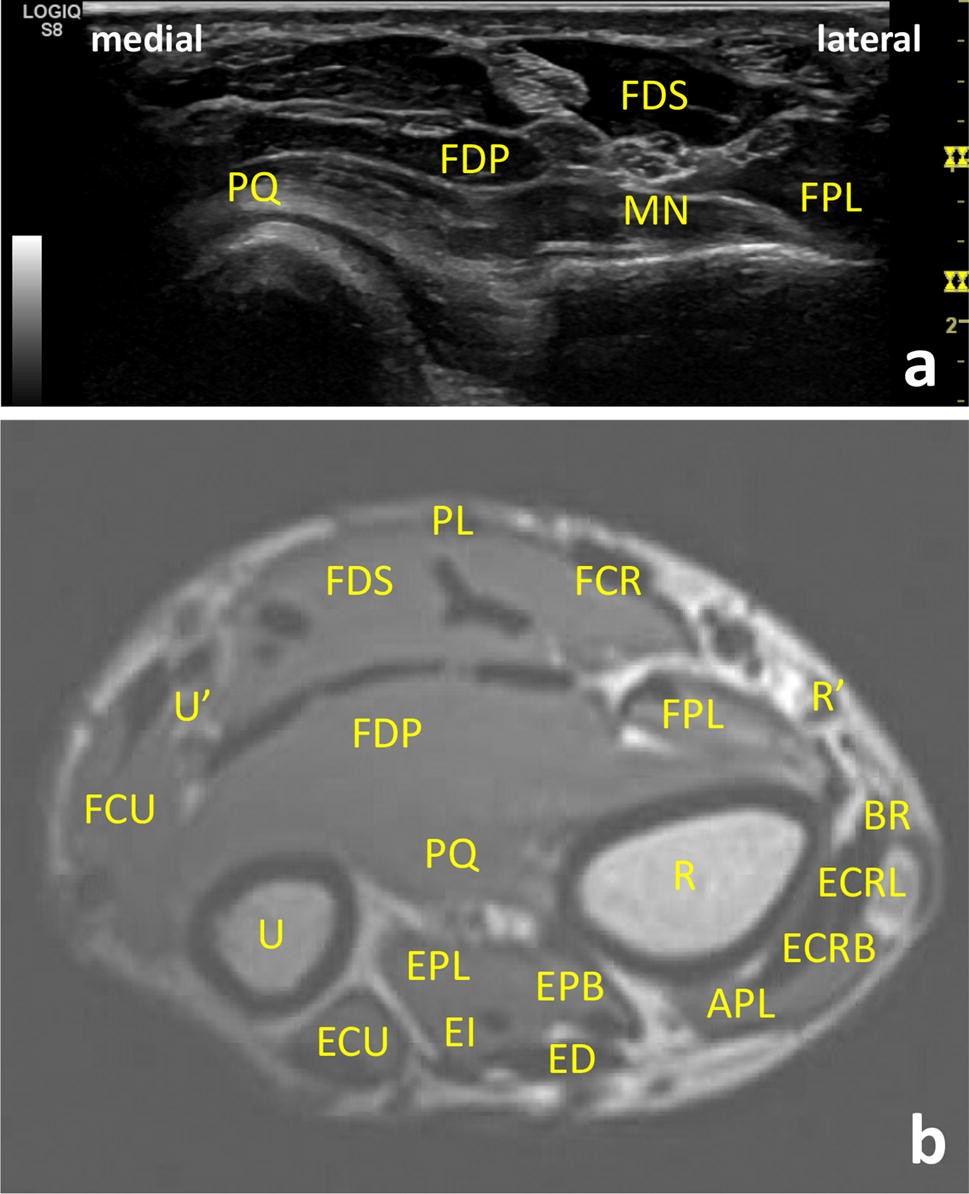

32+ Forearm Muscles Anatomy Mri. All superficial muscles are arises from the medial epicondyle of humerus but they are inserted into the different part except. Forearm fractures anatomy and assessment orthopaedicprinciples com.

Fortunately, there's some patterns that can make the forearm a little bit easier.

3d anatomy tutorial on the muscles of the flexor compartment of the forearm. The brachioradialis is a muscle of the forearm that flexes the forearm at the elbow. Mri of the upper limb. Magnetic resonance imaging (mri) utilizes magnet and radio waves to produce diagnostic images that allow a doctor to visualize the hips.